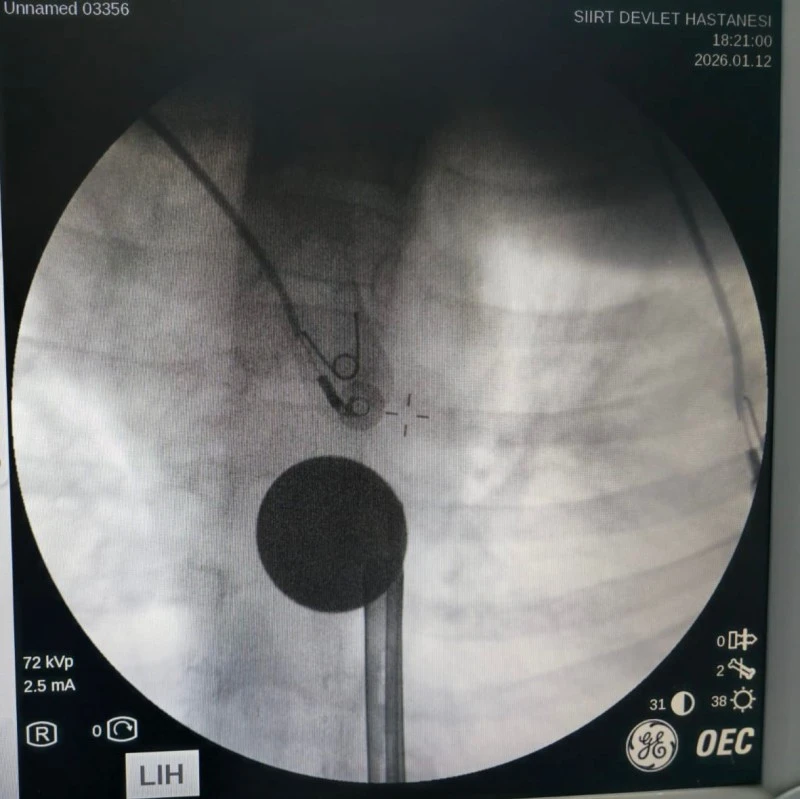

Tetkiklerde, 5 TL’lik madeni paranın yemek borusuna kadar ilerlediği belirlendi. Bunun üzerine Gastroenteroloji Uzmanı Dr. Yaren Dirik ile Kulak Burun Boğaz (KBB) Hekimi Dr. Yasin Gökçınar’ın ortaklaşa gerçekleştirdiği girişimle madeni para, herhangi bir komplikasyona yol açmadan çıkarıldı.

Siirt Eğitim ve Araştırma Hastanesi Başhekim Yardımcısı Uzman Dr. Burak Özkan, çocuk hastalarda yabancı cisim yutma vakalarının ciddi riskler taşıyabildiğine dikkat çekerek, “Hastanemize başvuran 8 yaşındaki hastamızın yemek borusuna kaçan madeni para, gastroenteroloji ve KBB ekiplerimizin titiz ve koordineli çalışmasıyla başarıyla çıkarılmıştır. Operasyon sorunsuz geçmiş, hastamızın genel durumu iyidir,” dedi.